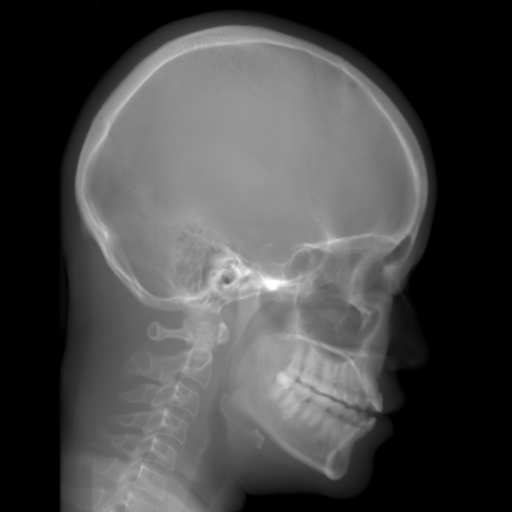

5.2 Head Data

Refer to caption

(a) Reference

(b) 0superscript00^{\circ} perspective

(c) (b)-(a)

7.80, 0.9093

Pix2pixGAN Prediction

(d) 0superscript00^{\circ} Cartesian

(e) 0&180superscript0superscript1800^{\circ}\&180^{\circ} Cartesian

(f) 0&180superscript0superscript1800^{\circ}\&180^{\circ} polar

6.06, 0.9249

2.99, 0.9820

2.07, 0.9842

Pix2pixGAN difference

(g) (d)-(a)

(h) (e)-(a)

(i) (f)-(a)

TransU-Net Prediction

(j) 0superscript00^{\circ} Cartesian

(k) 0&180superscript0superscript1800^{\circ}\&180^{\circ} Cartesian

(l) 0&180superscript0superscript1800^{\circ}\&180^{\circ} polar

6.45, 0.9356

2.36, 0.9864

3.65, 0.9734

TransU-Net Difference

(m) (j)-(a)

(n) (k)-(a)

(o) (l)-(a)

Figure 11: Perspective deformation learning in one exemplary patient case for cephalometric imaging. In (b), the left and right sides of the mandible do not overlap well, as indicated by the arrow. In (c), a scale bar of 2 mm is displayed (zoom in for better visualization), as 2 mm is the clinically acceptable precision for cephalometric landmark detection. In (e), (h) and (j), incorrect areas are marked by the red arrows.

TABLE III: Quantitative evaluation of different methods on head data.

Method Metric 0superscript00^{\circ} input 0superscript00^{\circ} 0&180superscript0superscript1800^{\circ}\&180^{\circ} 0&180superscript0superscript1800^{\circ}\&180^{\circ}

perspective Cart. Cart. polar

Pix2pix RMSE 10.69 7.33 4.58 3.87

GAN SSIM 0.8680 0.9053 0.9476 0.9625

Trans RMSE 10.69 8.13 3.36 3.22

U-Net SSIM 0.8680 0.9257 0.9682 0.9719

The results of one exemplary patient for cephalometric imaging are displayed in Fig. 11. In the 0superscript00^{\circ} perspective projection image (Fig. 11(b)), because of perspective deformation, anatomical structures from the left and right sides do not overlap well, especially for the mandible as indicated by the red arrow in Fig. 11(b). It causes inaccuracy in determining the cephalometric landmark of the gonion. The difference of Fig. 11(b) to the reference Fig. 11(a) is displayed in Fig. 11(c). A scale bar of 2 mm is displayed in Fig. 11(c), as 2 mm is the clinically acceptable precision for cephalometric landmark detection. It is obvious that many anatomical structures in the 0superscript00^{\circ} perspective projection images have position shifts larger than 2 mm. In the prediction image (Fig. 11(d)) using a single 0superscript00^{\circ} view in Cartesian coordinates, perspective deformation is reduced to some degree, as displayed in the difference image Fig. 11(g). For example, the mandible region has less error. However, Fig. 11(g) also indicates that many bony structures still have deviations larger than 2 mm. The results of learning from dual complementary views in Cartesian and polar coordinates are displayed in Fig. 11(e) and Fig. 11(f), respectively. Both images have little perspective deformation, as revealed by their difference images in Fig. 11(h) and Fig. 11(i). Nevertheless, in Fig. 11(e), two dark regions are indicated by the two arrows, which are better visualized in the difference image Fig. 11(h). The results of TransU-Net are displayed in Figs. 11(j)-(o). In Fig. 11(m), the structures near the porion landmark are distorted, for example, the ear canal indicated by the arrow. Consistent with Pix2pixGAN, perspective deformation is largely reduced in the both TransU-Net prediction images using dual complementary views in Cartesian and polar coordinates.